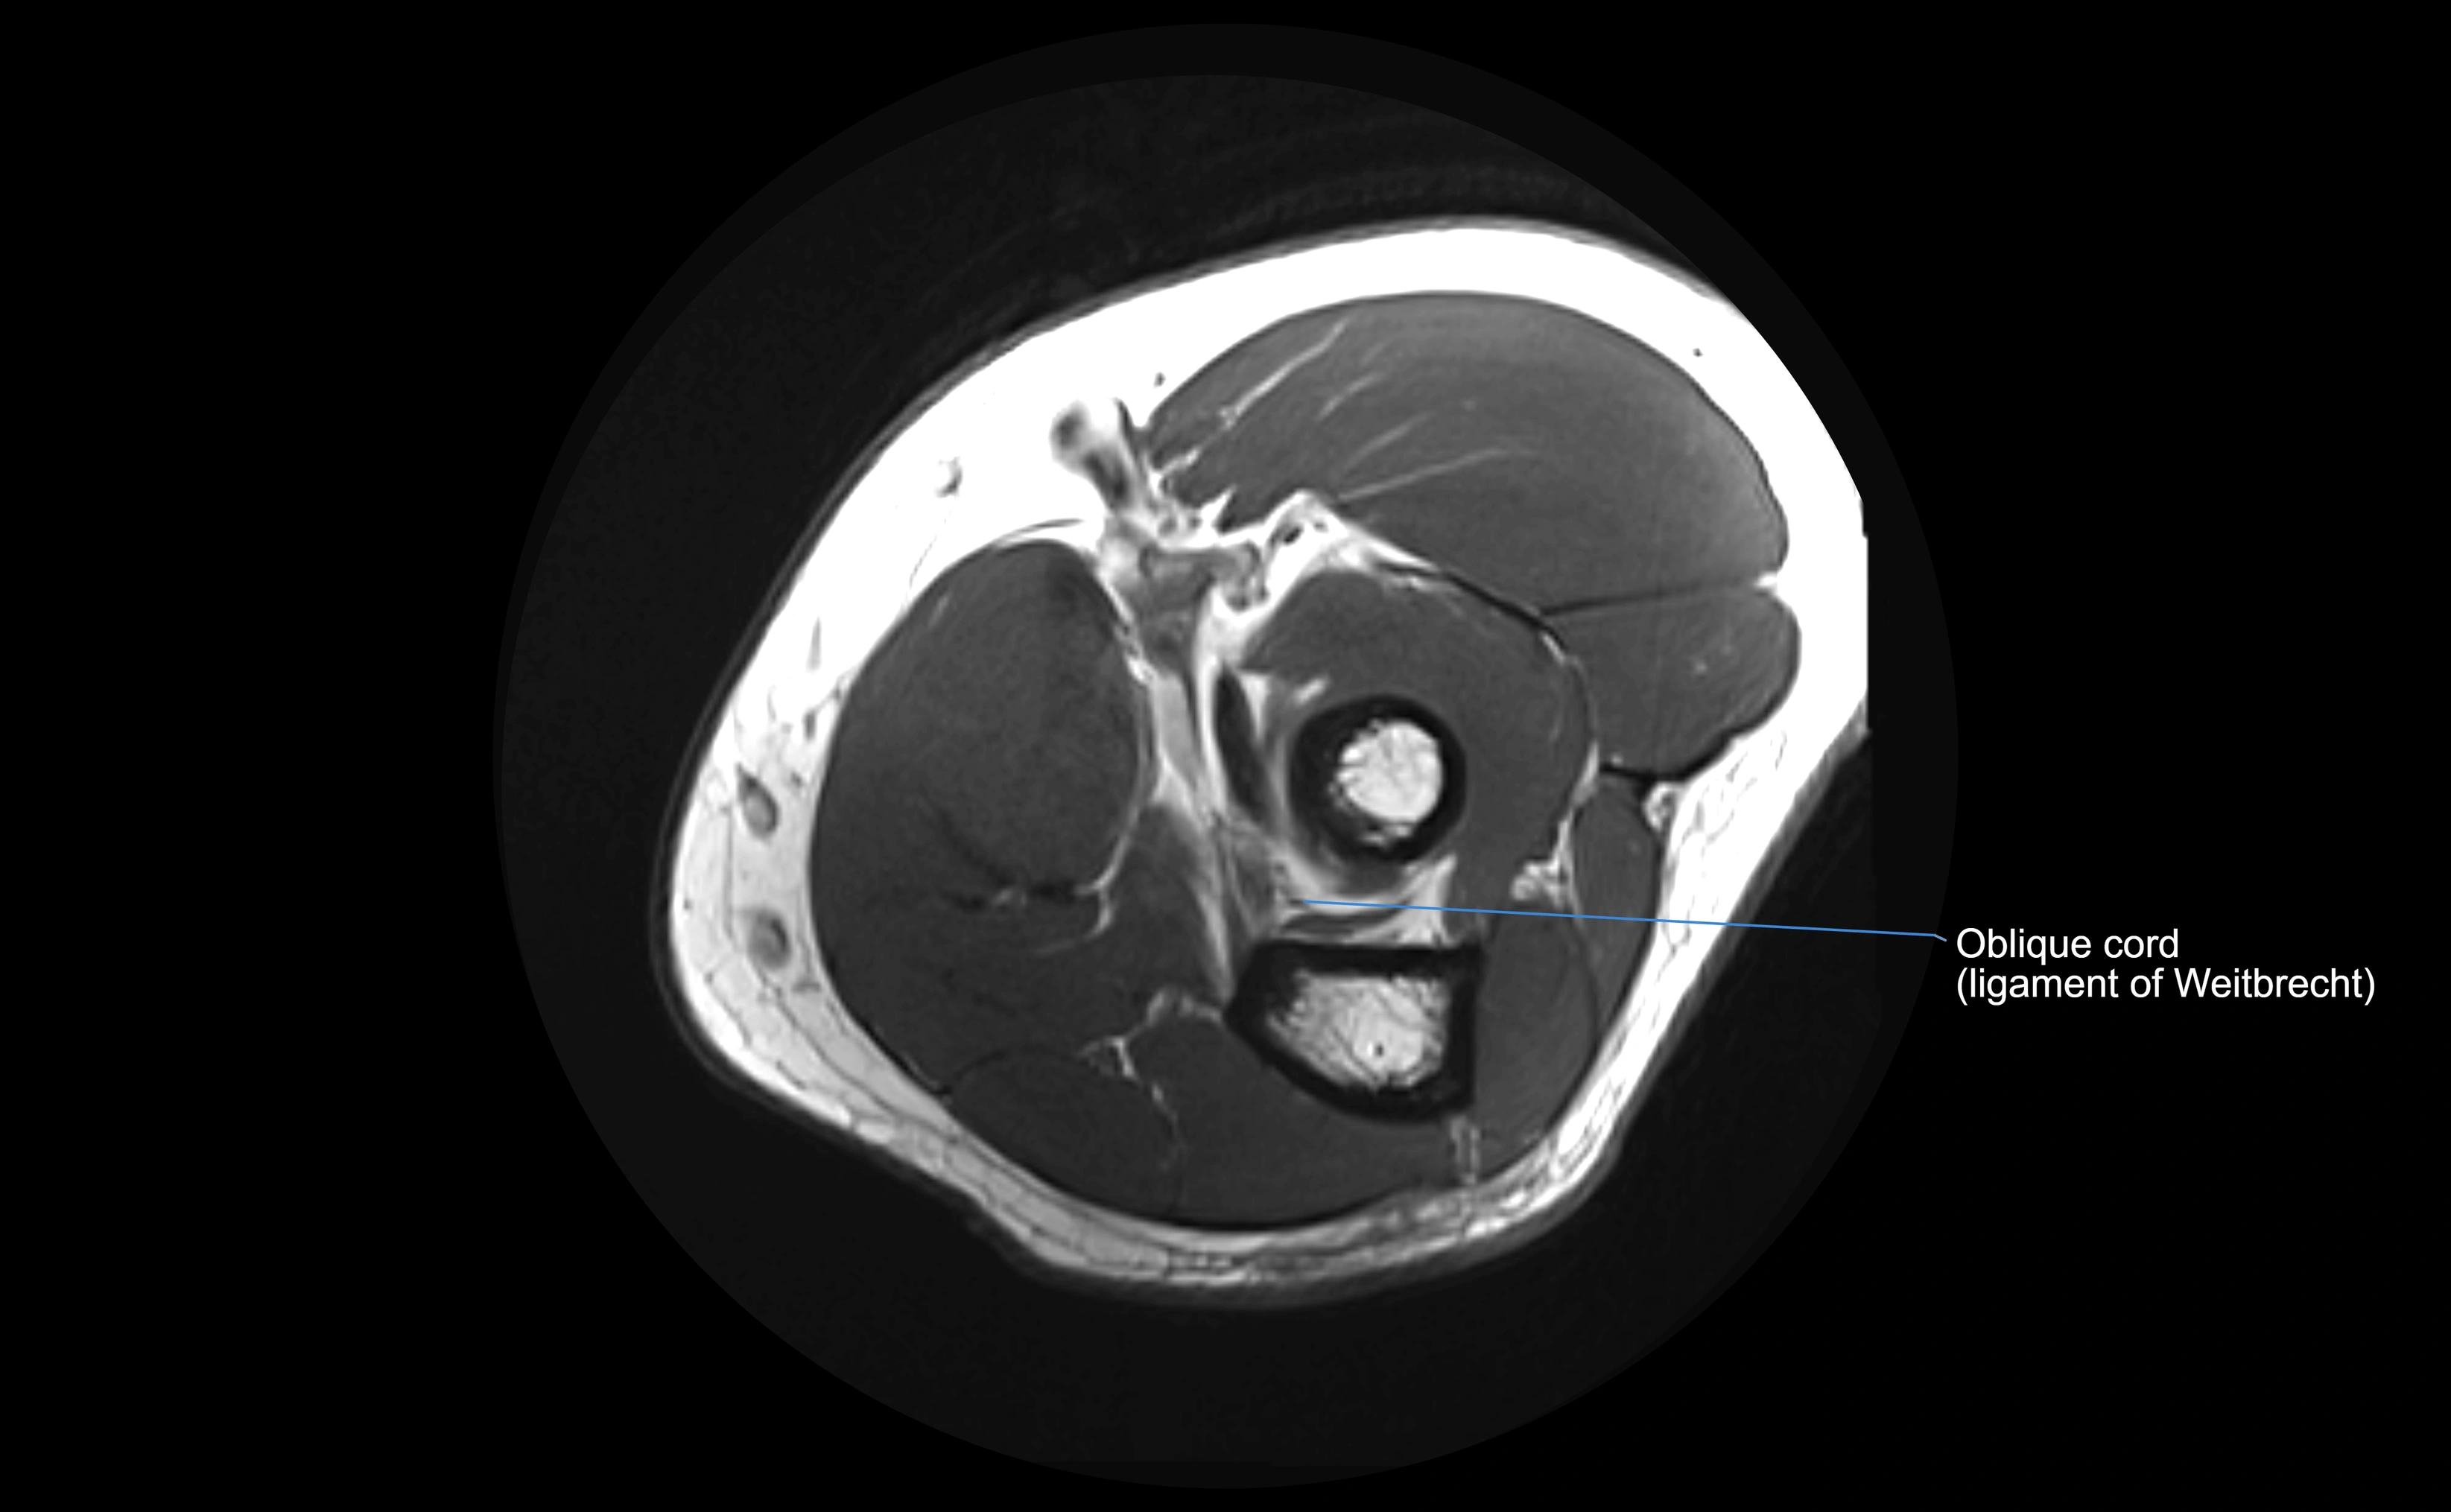

MRI images

image